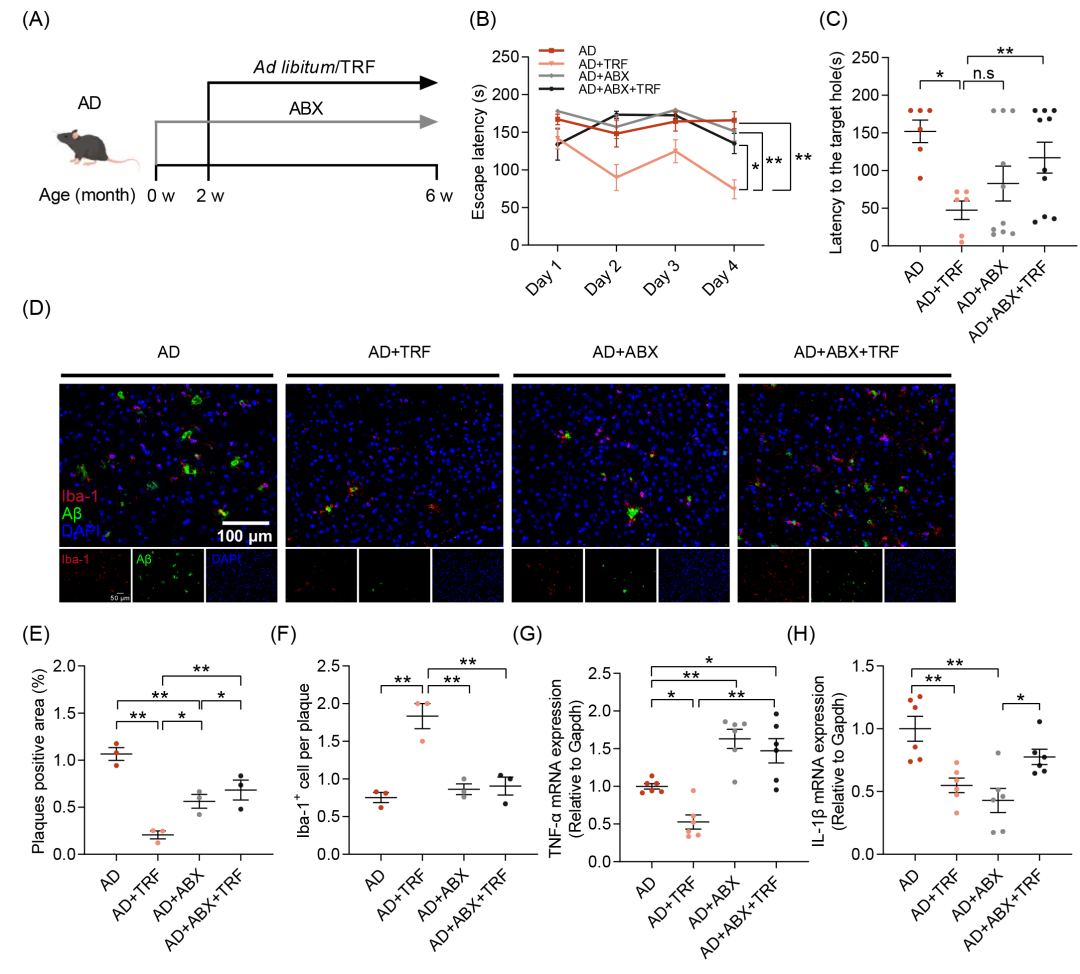

为了进一步验证肠道菌群在TRF改善AD小鼠认知功能障碍中的介导作用,本研究采用广谱抗生素(ABX)对小鼠进行2周的肠道菌群清除处理,随后进行4周的TRF干预。实验全程每日给予ABX,以确保肠道菌群的持续消除(图3A)。结果显示,肠道菌群的耗竭消除了TRF对AD小鼠认知障碍的改善作用,这一现象可通过巴恩斯迷宫的逃避潜伏期、到达目标孔的潜伏期以及接近目标孔的次数等指标加以验证(图3B、C和图S5D)。此外,相较于AD+TRF组,仅接受抗生素处理的AD小鼠未表现出认知能力的显著改善(图3B)。免疫荧光染色结果显示,尽管ABX干预可减少Aβ沉积,其作用相较于TRF干预仍较为有限(图3D-F和图S5F,G)。肠道菌群的耗竭消除了TRF对AD病理损伤的改善作用(图3D-F和图S5F-H),并阻断了TRF诱导的小胶质细胞向Aβ斑块的募集(图3D-F和图S5F-H)。抗生素处理对脑内神经炎症因子的表达产生显著影响,表现为TNF-α水平的上升及IL-1β水平的下降(图3G,H)。然而,在TRF干预下,TNF-α和IL-1β均显著降低,而这一效应在去除肠道菌群后消失(图3G,H)。结果表明,肠道菌群在TRF对AD小鼠认知功能障碍的保护作用中发挥着关键调控作用。

图3. 肠道菌群移除会消除TRF对AD小鼠的改善作用

(A)每组接受广谱抗生素(ABX)和TRF干预的实验流程示意图(n = 6-10);(B)逃避潜伏期;(C)到达目标孔的潜伏期;(D)小鼠皮层中Aβ沉积(绿色)及Iba-1+阳性小胶质细胞(红色)的免疫荧光染色图像(n = 3)(比例尺:100 μm);(E)Aβ斑块阳性区域的定量分析;(F)Aβ斑块相关小胶质细胞的定量分析;(G)TNF-α的mRNA水平测定(n = 6);(H)IL-1β的mRNA水平测定(n = 6)。数据以均值 ± SEM表示。*p < 0.05,**p < 0.01;单因素方差分析(one-way ANOVA)结合Tukey多重比较检验。